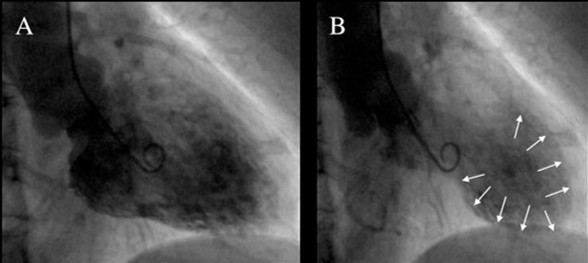

左心室造影显示出舒张期(A)及收缩期末(B)LV中部和心尖部的典型形态。在收缩期末,心尖部和LV下段(箭头所示)可明显看到动脉瘤样扩张(气球样);因此,TCM也被称为“心尖球形综合征”。

收缩期左心室造影显示特性心尖部球样扩张伴心尖室壁运动缺失(箭头)。

典型TCM的变异型已被识别,但其发生率一般较典型TCM低。反向TCM患者的左心室造影显示存在心尖运动增强和基底部运动缺失,而不是典型的TCM心尖扩张(球样)运动缺失和基底部运动增强。A图为舒张期影像,B图为收缩期影像。箭头所示为心尖部正常的心室运动。